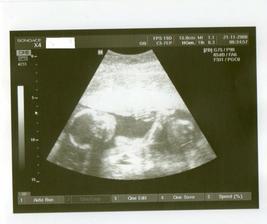

19.8...........1.ultrazvuk-gestační váček

28.8............2.UTZ--srdíčko už tlouklo,mimimnko je 7+3 a rozloučila jsem se se všemi v Podolí a ted už jen ke své gynekoložce

18.9...........UTZ,miminko je krásně vidět🙂)))je 10+5 a máme průkajdu......

26.9...........UTZmiminko kope nožičkama a mává ručičkama---nádhera.Je trošku starší..12+1